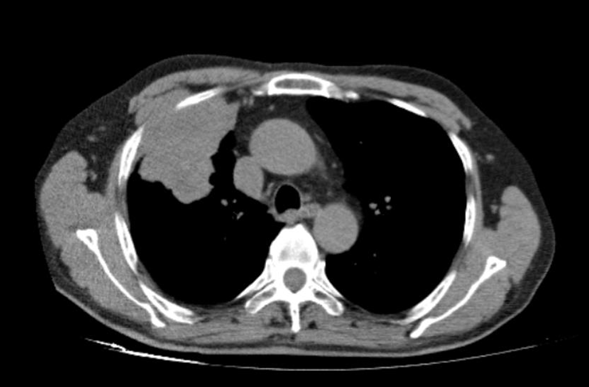

患者为69岁男性,吸烟史长达55包年,患有慢性阻塞性肺疾病(COPD),因背痛2月余入院。2021年12月,胸部CT和脑部MRI检查发现右侧上叶占位性病变,大小为68×66mm,并伴有右侧额颞部低密度病灶。2022年1月,PET-CT显示右侧上叶病灶增大至84×50mm,SUVmax为15.7,纵隔淋巴结(右侧气管旁、主动脉肺动脉、血管周围、气管旁)受累,SUVmax为3.15,右侧肾上腺转移灶大小为33×40mm,SUVmax为11.1。